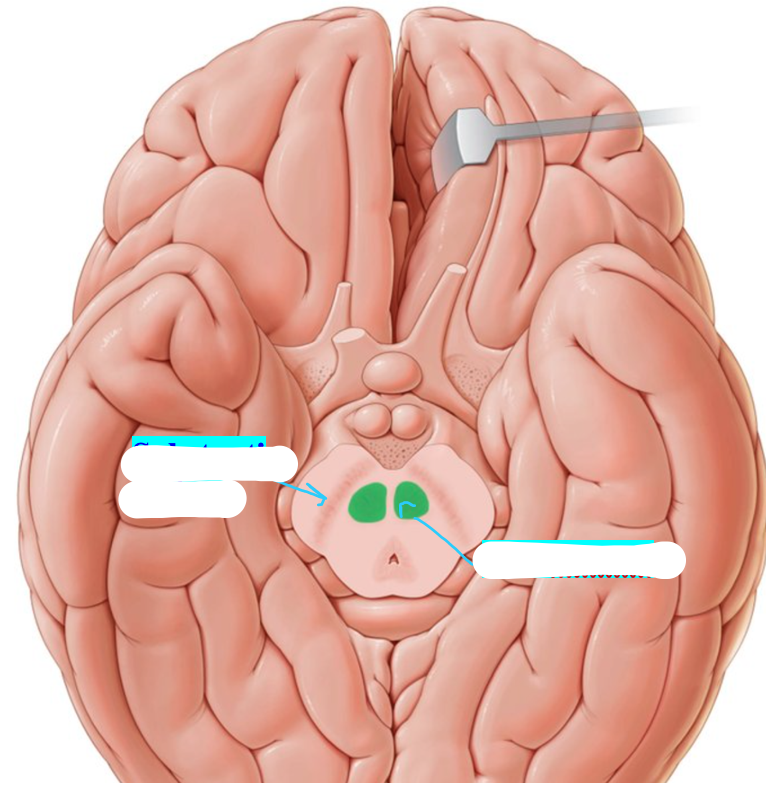

What is the structure called highlighted in red

Substantia nigra